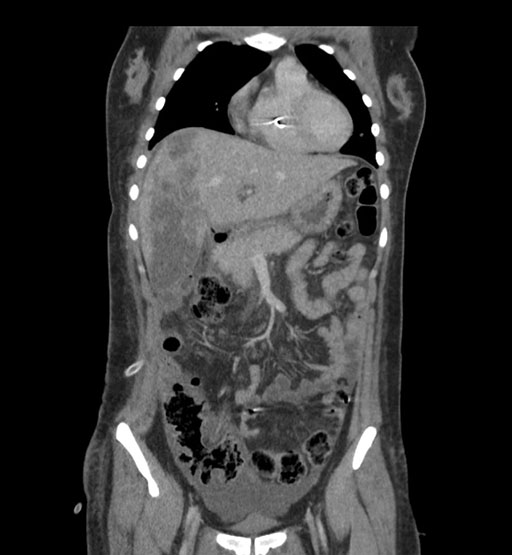

Coronal Arterial

Coronal Venous